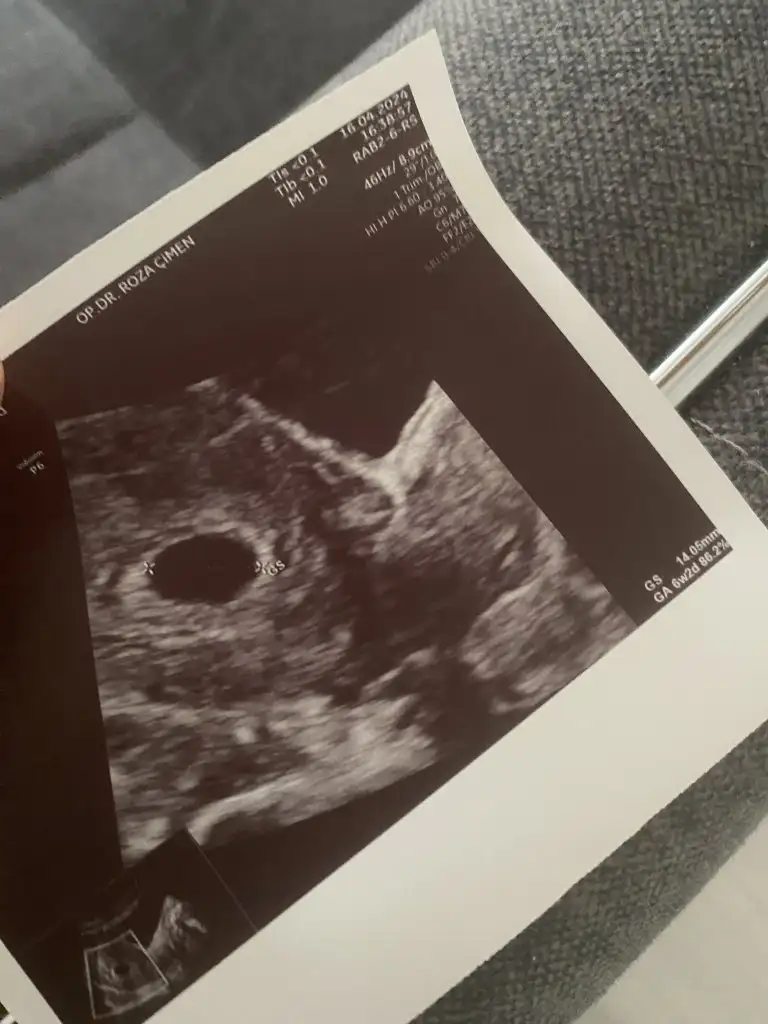

Merhaba 5 haftalıkken kontrole gittim kese gayet iyi dedi de embriyo hakkın da bilgi vermedi. Tüp bebek yaptık korkuyorum boş gebelik olur diye. Bakar mısız sizce bebek var mı?

5 haftalıkken bebek görünmemesi normal. Doktor her şey yolunda dediyse her şey iyidir. Canınızı sıkmayın daha çok erken

Bu kese boş değil🥰 2kez boş gebelik yaşadım kesenin içi simsiyah ve boştu . Güzel haberler alın inşallah